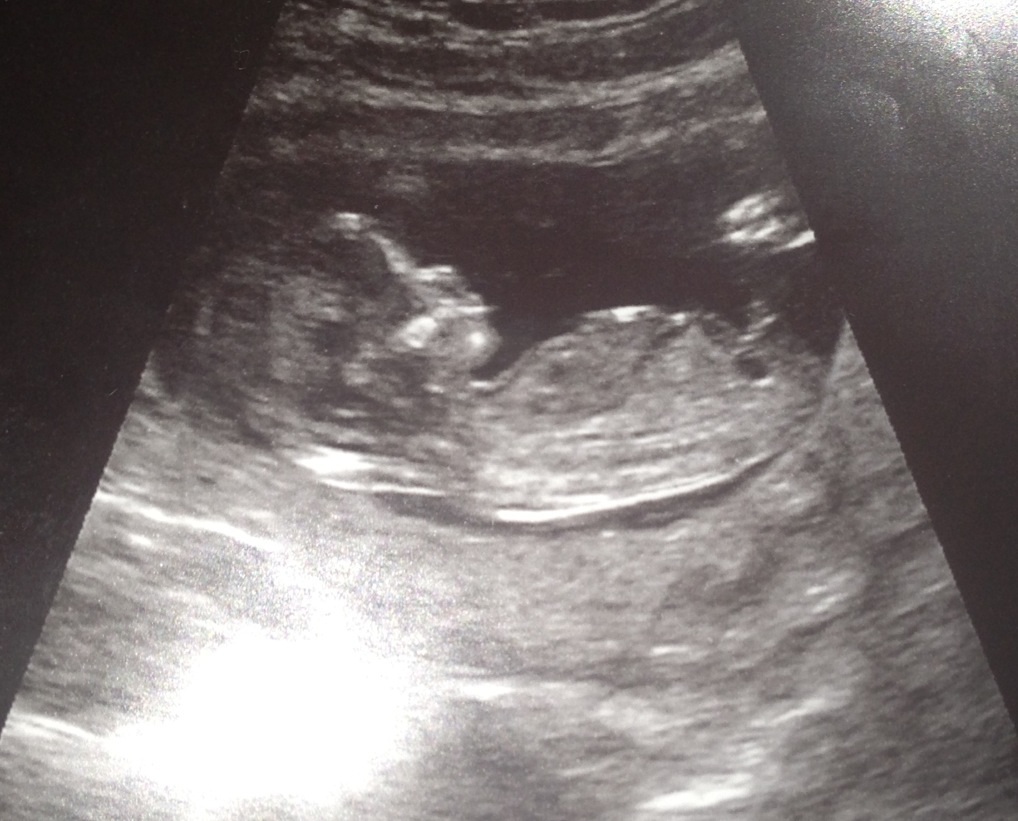

I went to the Dr. today and they made a rule where they wont tell you gender untill 18-20 weeks!!! GRRR!!! No guesses nothing! I have no clue what Im looking at! What do you ladies think? Boy#4 or Girl#1????

Attachment 10433

Attachment 10434

Attachment 10435